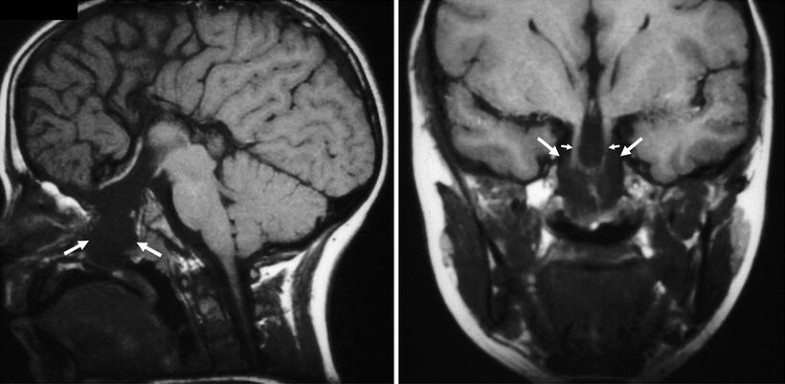

Transsphenoidal encephalocele. (a) T1-weighted sagittal MR image shows an encephalocele extending down through the sphenoid bone into the nasopharynx with impression on the hard palate (white arrows). (b) T1-weighted coronal MR image shows the third ventricle and hypothalamus extending inferiorly into the encephalocele (delimited inferiorly by open arrows). Used, with permission, from Barkovich [19]. Photographs courtesy of A. James Barkovich, M.D.